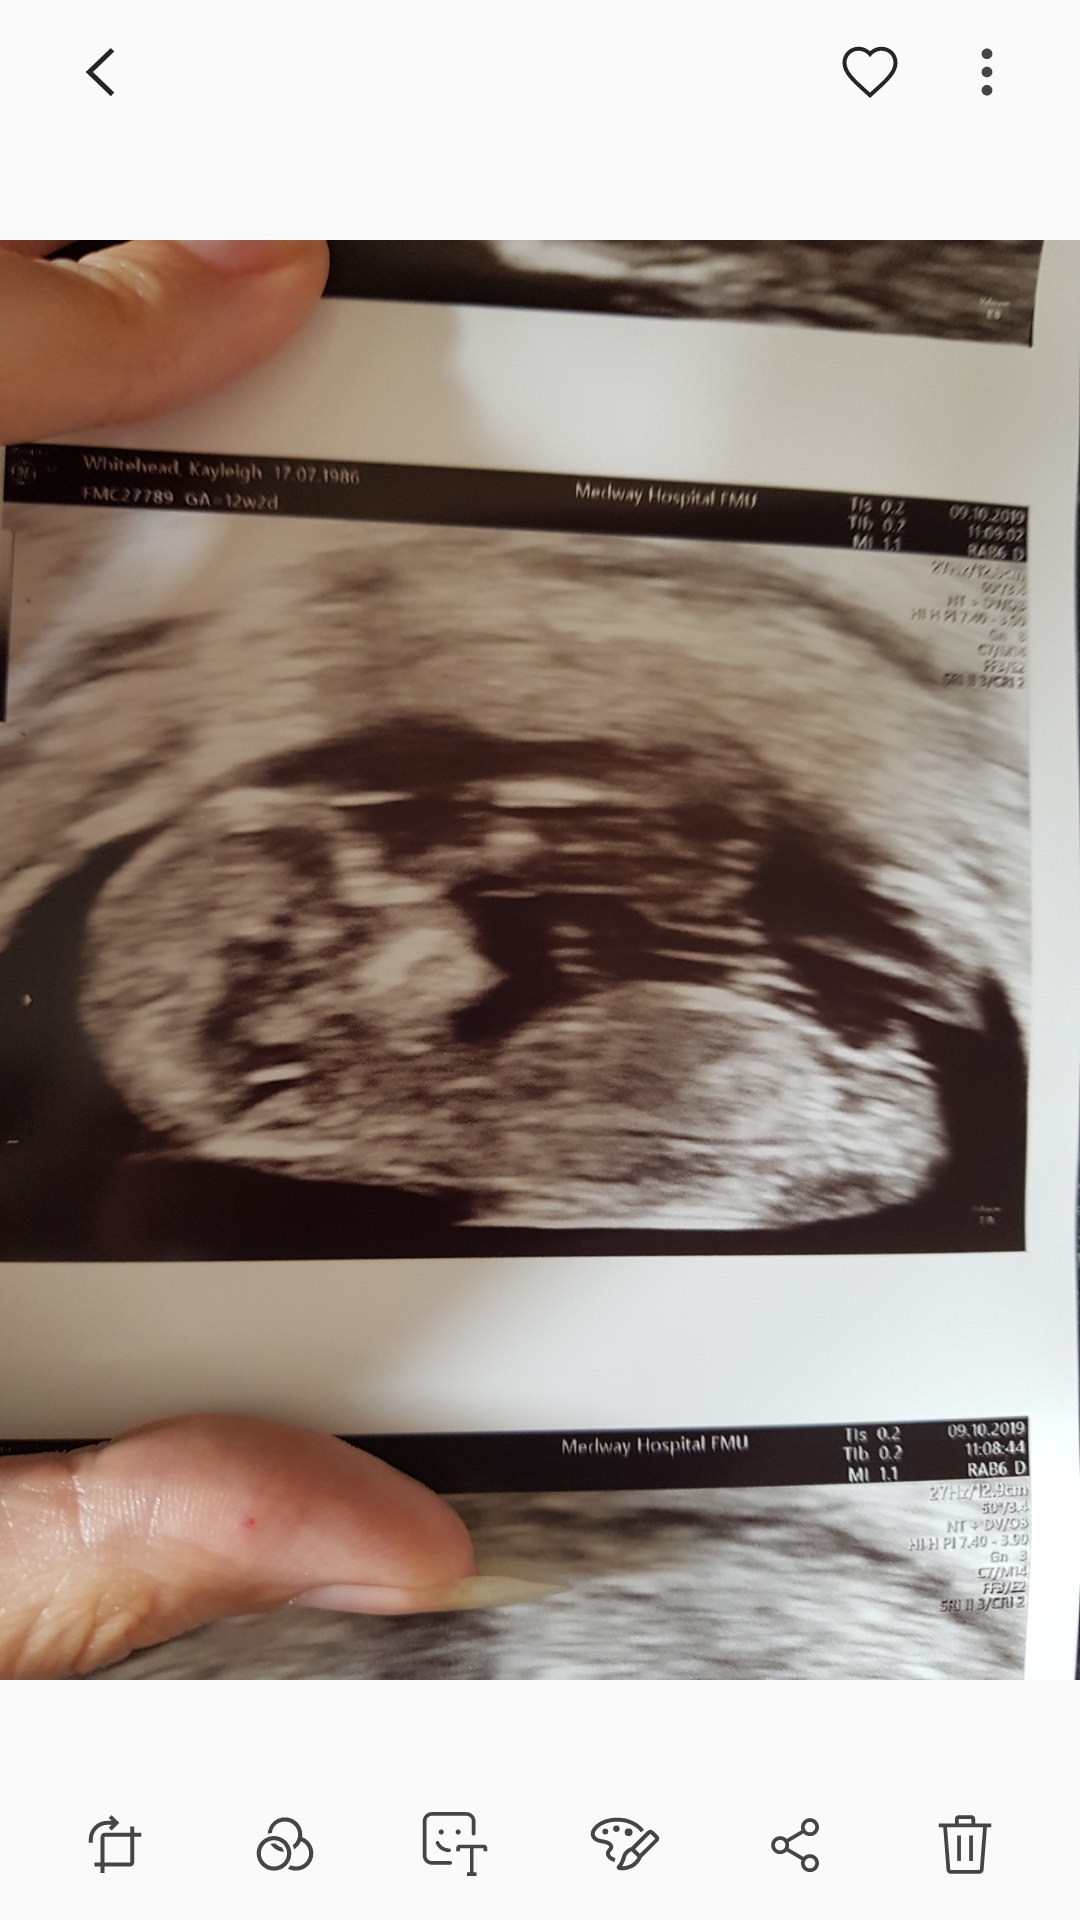

Baby was upside down so not sure if it makes a difference. 13 weeks exactly. What do you all think? Boy 5 or? I feel like the nub looked really long and flat at some points in the scan and even that I saw forking, but I'm not sure if what I saw was actually stacking and I just wanted it to be forking

Another picture added to page 2.